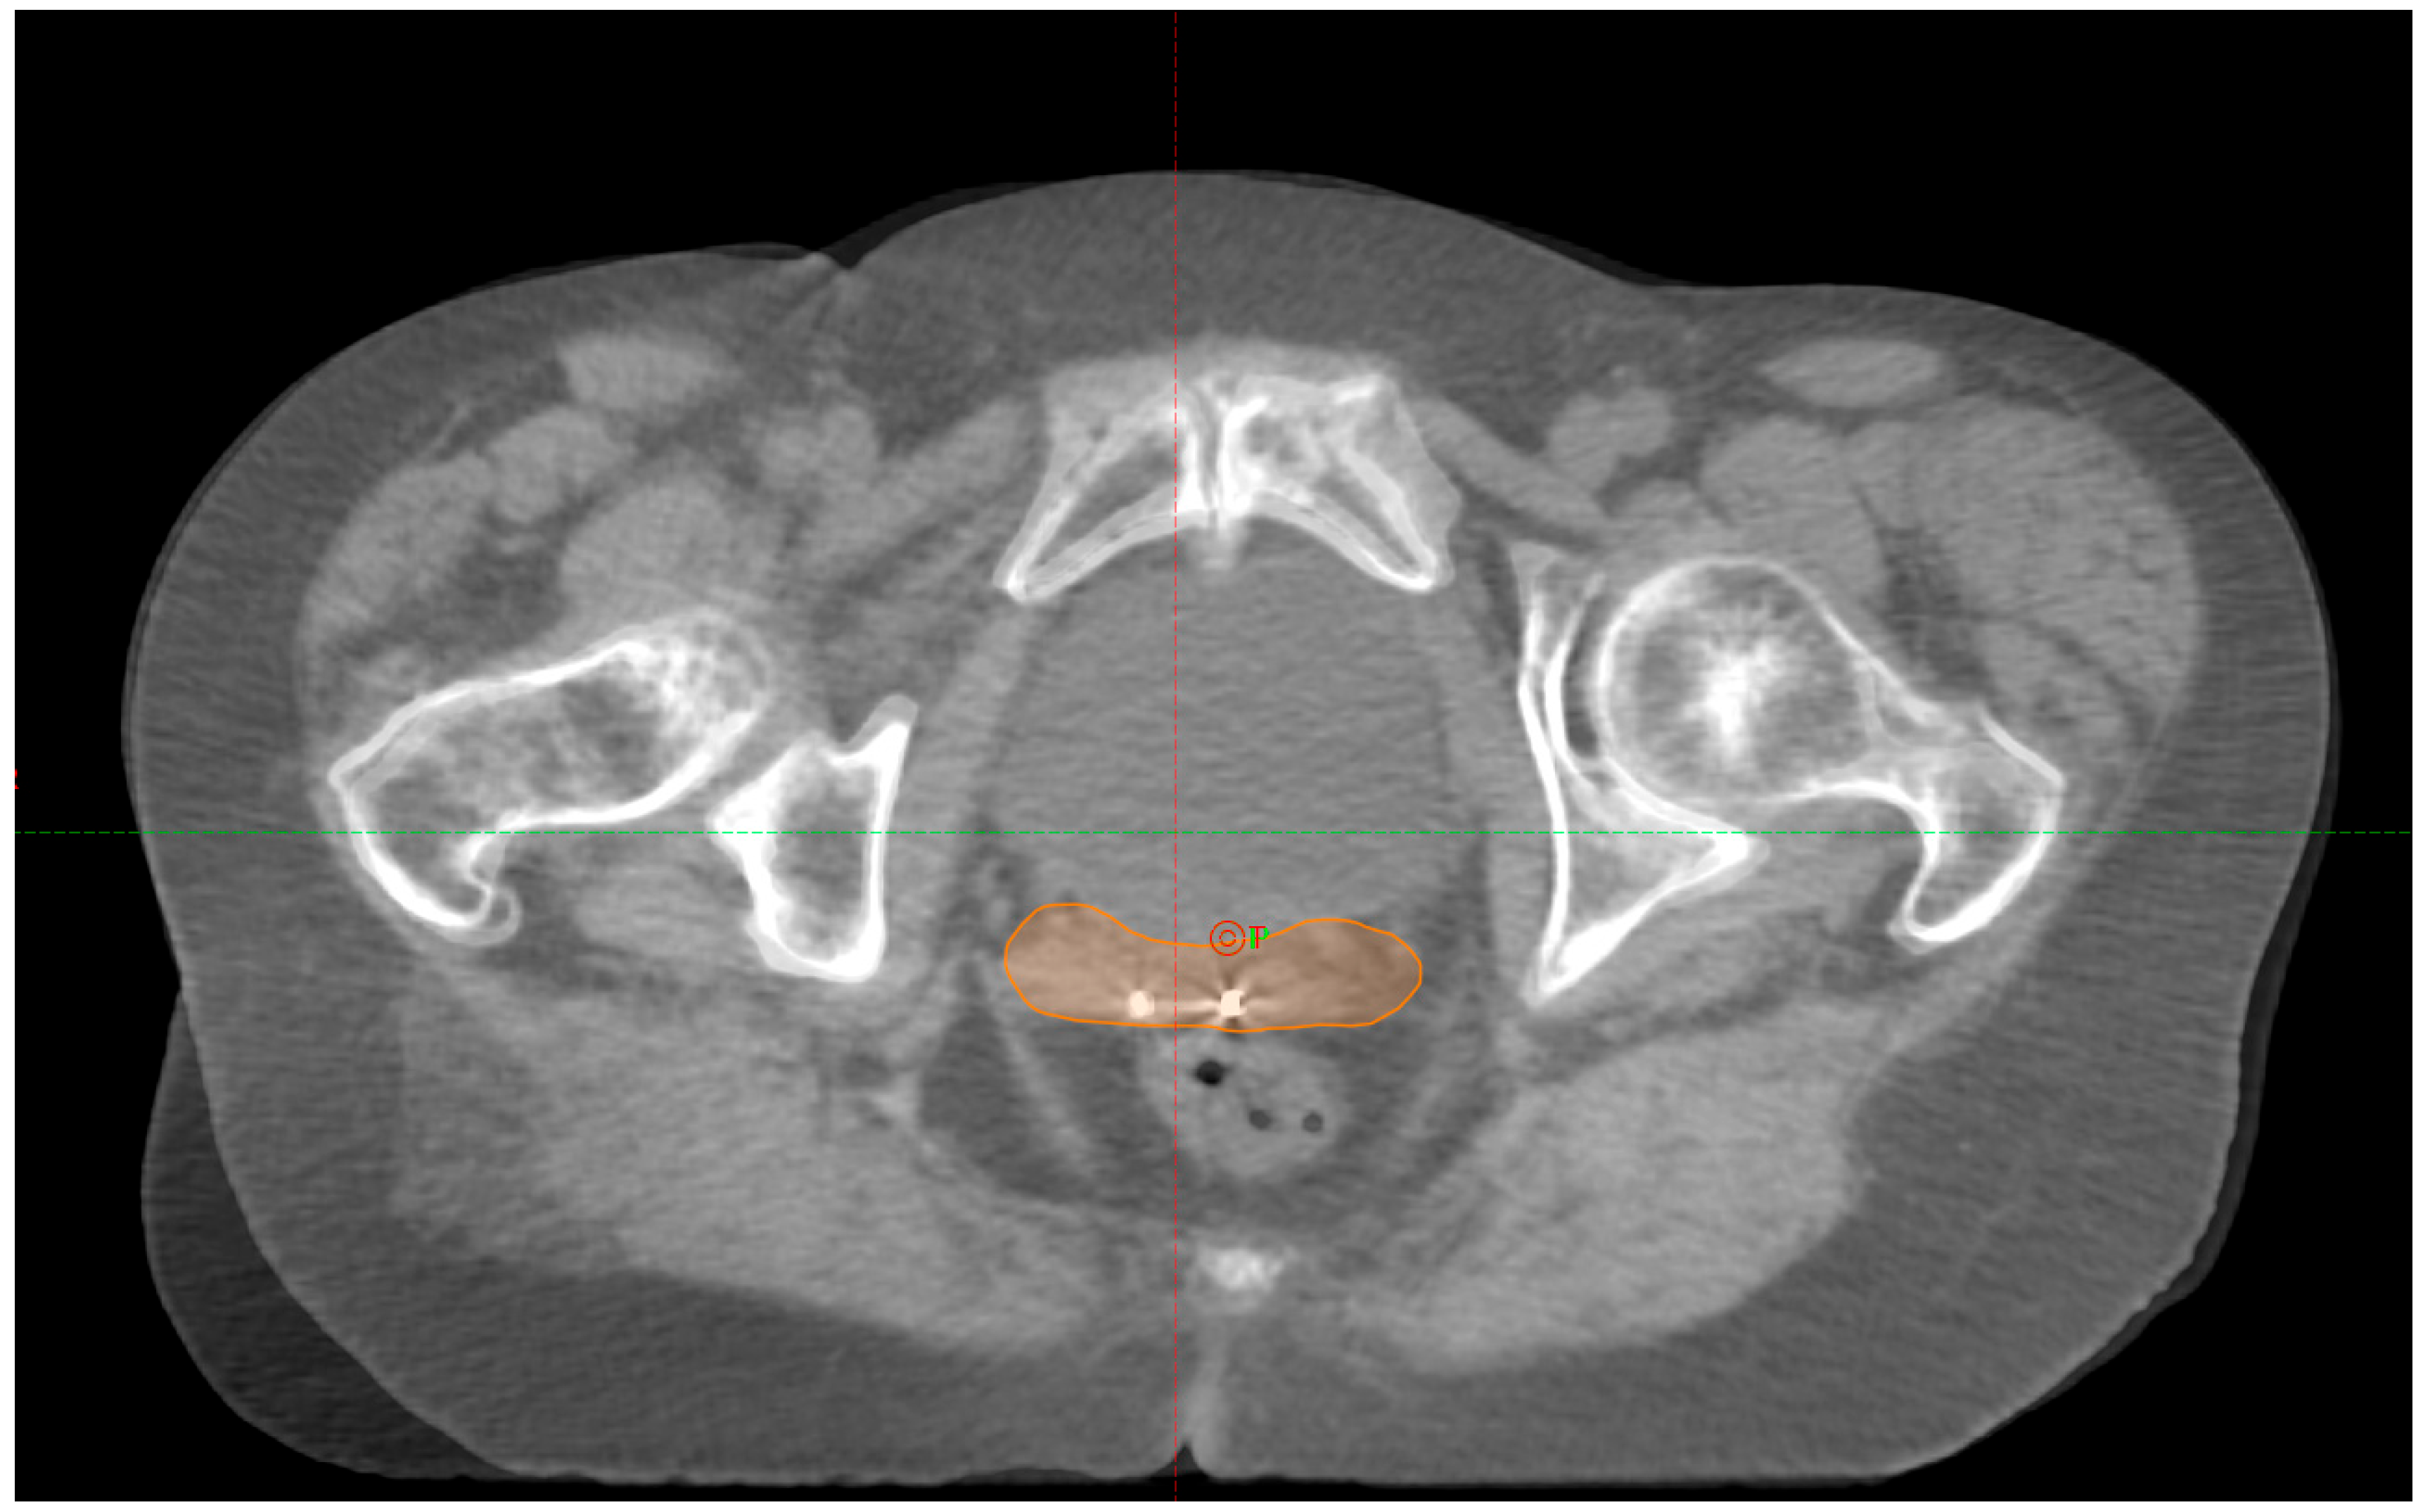

We did not observe any loss of FMs during or before treatment. A total of twenty CBCTs were analyzed across ten fractions (in Figure 1, there is an example of match pCT-CBCT). In one patient, the treatment delivery was postponed to the following day because of an unsatisfactory preparation level of the rectum.

Figure 1. An example of the IGRT technique applied in this observational study (pt4—fraction 2); pCT imaging with the vaginal CTV segmented registered with daily CBCT based on the alignment of the implanted FMs.